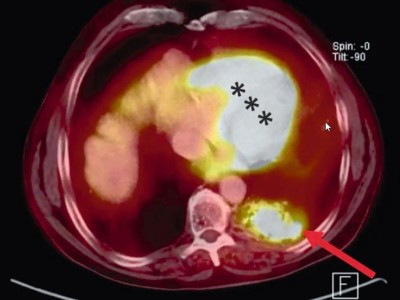

Einsatz von funktioneller Bildgebung zur Therapieplanung

Funktionelle Bildgebung hat in den letzten Jahren immer mehr Bedeutung in der onkologischen Therapieplanung gewonnen. Die Positronenemissionstomographie (PET), meist kombiniert mit einer Computertomographie (PET-CT), ermöglicht häufig nicht nur …

Operation/© andrys lukowski / stock.adobe.com (Symbolbild mit Fotomodell), Arzt impft Patient/© FG Trade / Getty Images / iStock (Symbolbild mit Fotomodell), Koloskopie/© Kzenon / stock.adobe.com (Symbolbild mit Fotomodellen), Bestrahlungsplans einer Wirbelsäulenmetastase eines oligometastasierten Prostatakarzinoms/© Springer Medizin Verlag GmbH, Blutprobe wird bei Patient abgenommen/© Tashi-Delek / Getty Images / iStock(Symbolbild mit Fotomodellen), Endobronchialer Befund mit exophytischem Tumor im Bereich des rechten Oberlappens/© Möller, M., Schütte, W. / all rights reserved Springer Medizin Verlag GmbH, Eine ältere Frau bekommt eine intravenöse Therapie/© peopleimages.com / stock.adobe.com, Mann gibt Anweisungen auf Baustelle/© Oliver Raupach - Fotolia (Symbolbild mit Fotomodell), CT-Thorax mit Verdacht auf Lungenkrebs/© Springer Medizin Verlag GmbH, Nicht-kleinzelliges Bronchialkarzinom/© windcatcher / Getty Images / iStock, Immuncheckpointinhibitoren binden an Krebszelloberflächenproteine /© Juan Gärtner / stock.adobe.com, Einem Mann wird Fieber gemessen/© eggeeggjiew / Getty Images / iStock (Symbolbild mit Fotomodell), Mann stützt den Kopf in die Hände/© Charday Penn / Getty Images / iStock (Symbolbild mit Fotomodell), Bronchoskopie/© Schroll S et al. / all rights reserved Springer Medizin Verlag GmbH, NSCLC in der PET-CT/© A. Schäffler, Bestrahlung eines Lungenkarzinoms/© Springer Medizin Verlag GmbH, Bildgebung einer rechts pulmonalen Raumforderung der Lunge/© Klotz, L.V., Welcker, K. / all rights reserved Springer Medizin Verlag GmbH, Search Icon, Endoskopische Befunde des Magenkarzinoms/© Probst, A., Messmann, H. / all rights reserved Springer Medizin Verlag GmbH, Hand hält Laborröhrchen/© Kunstzeug / stock.adobe.com (Symbolbild mit Fotomodell), Radiologin richtet Mammographiescreening ein/© LIGHTFIELD STUDIOS / stock.adobe.com (Symbolbild mit Fotomodellen), Diffus großzelliges B-Zell-Lymphom (DLBCL)/© David A Litman / stock.adobe.com